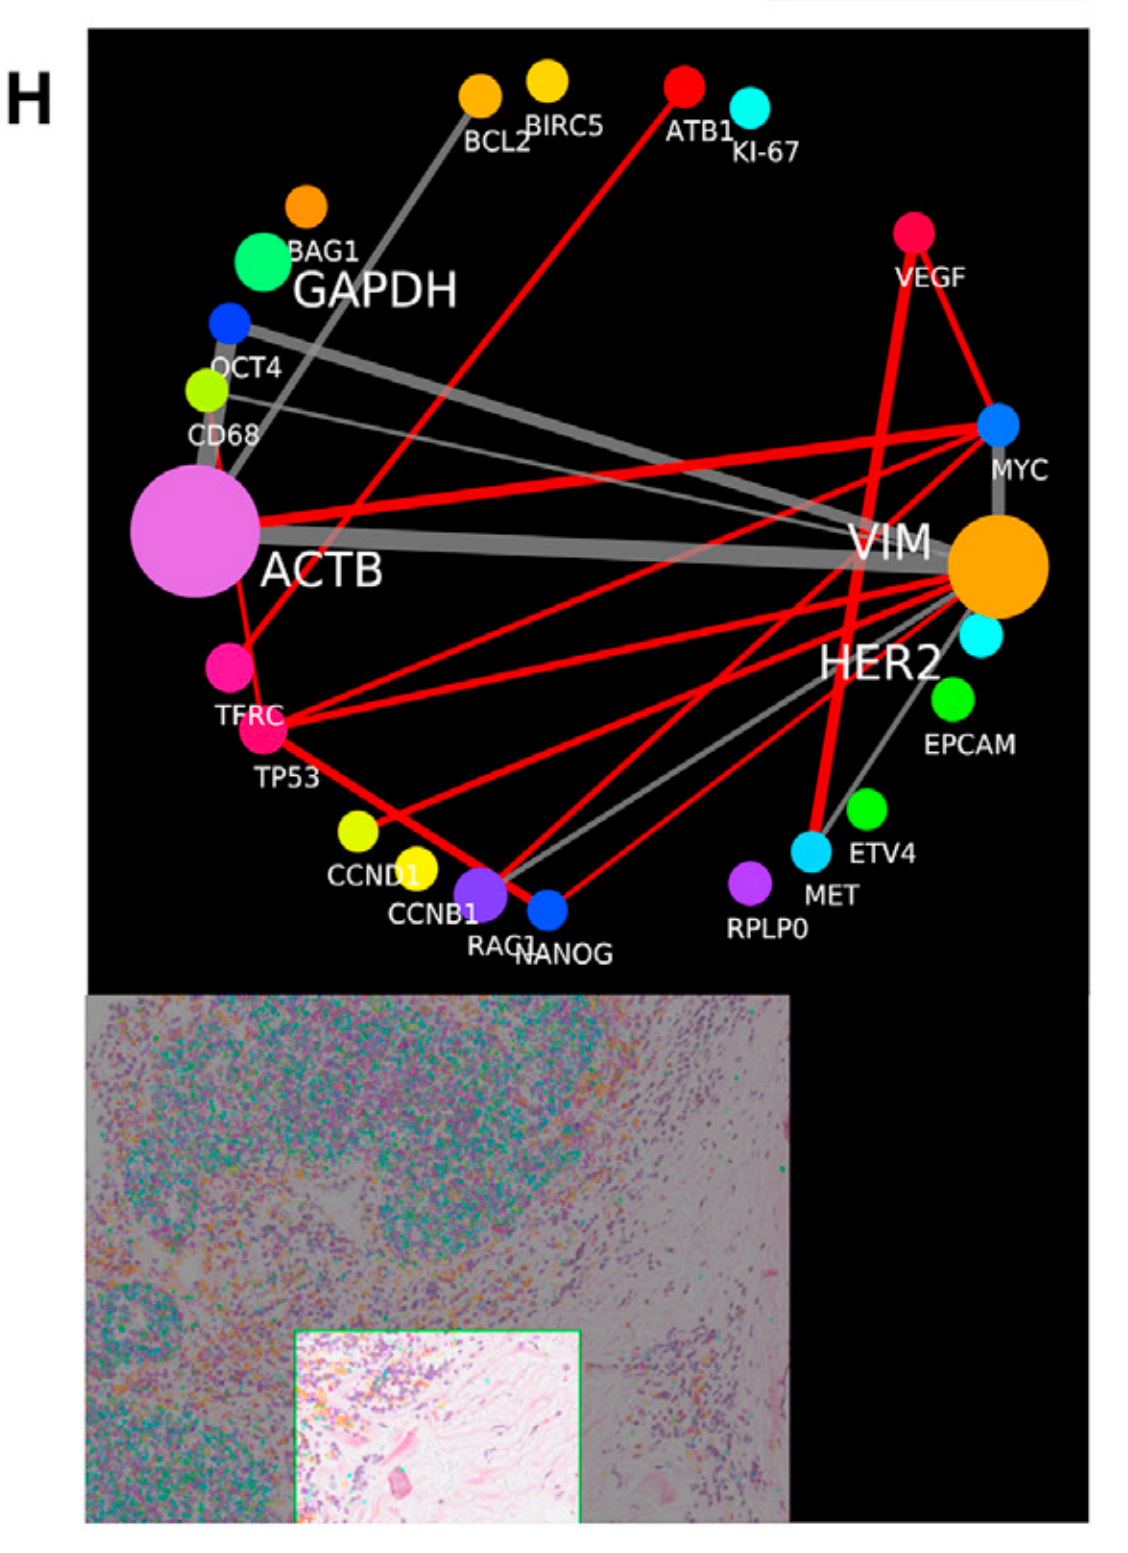

Li X. et al. - 2025

SPEX: A modular end-to-end platform for high-plex tissue spatial omics analysis

Condition Dimension

Categorical

Data Components

Biological AnnotationGene Expression Matrix

Metadata

None

Modality

Proteomics

Resolution of observation

Cellular

Visualized Elements

Statistic

How does expression of a gene differ across patient categories?

Li X. et al. - 2025

SPEX: A modular end-to-end platform for high-plex tissue spatial omics analysis

Condition Dimension

N/A

Data Components

Gene Expression Matrix

Data

Metadata

None

Modality

Proteomics

Resolution of observation

Cellular

Visualized Elements

FeatureObservation

Where are specific proteins expressed in both expression space and physical tissue space?